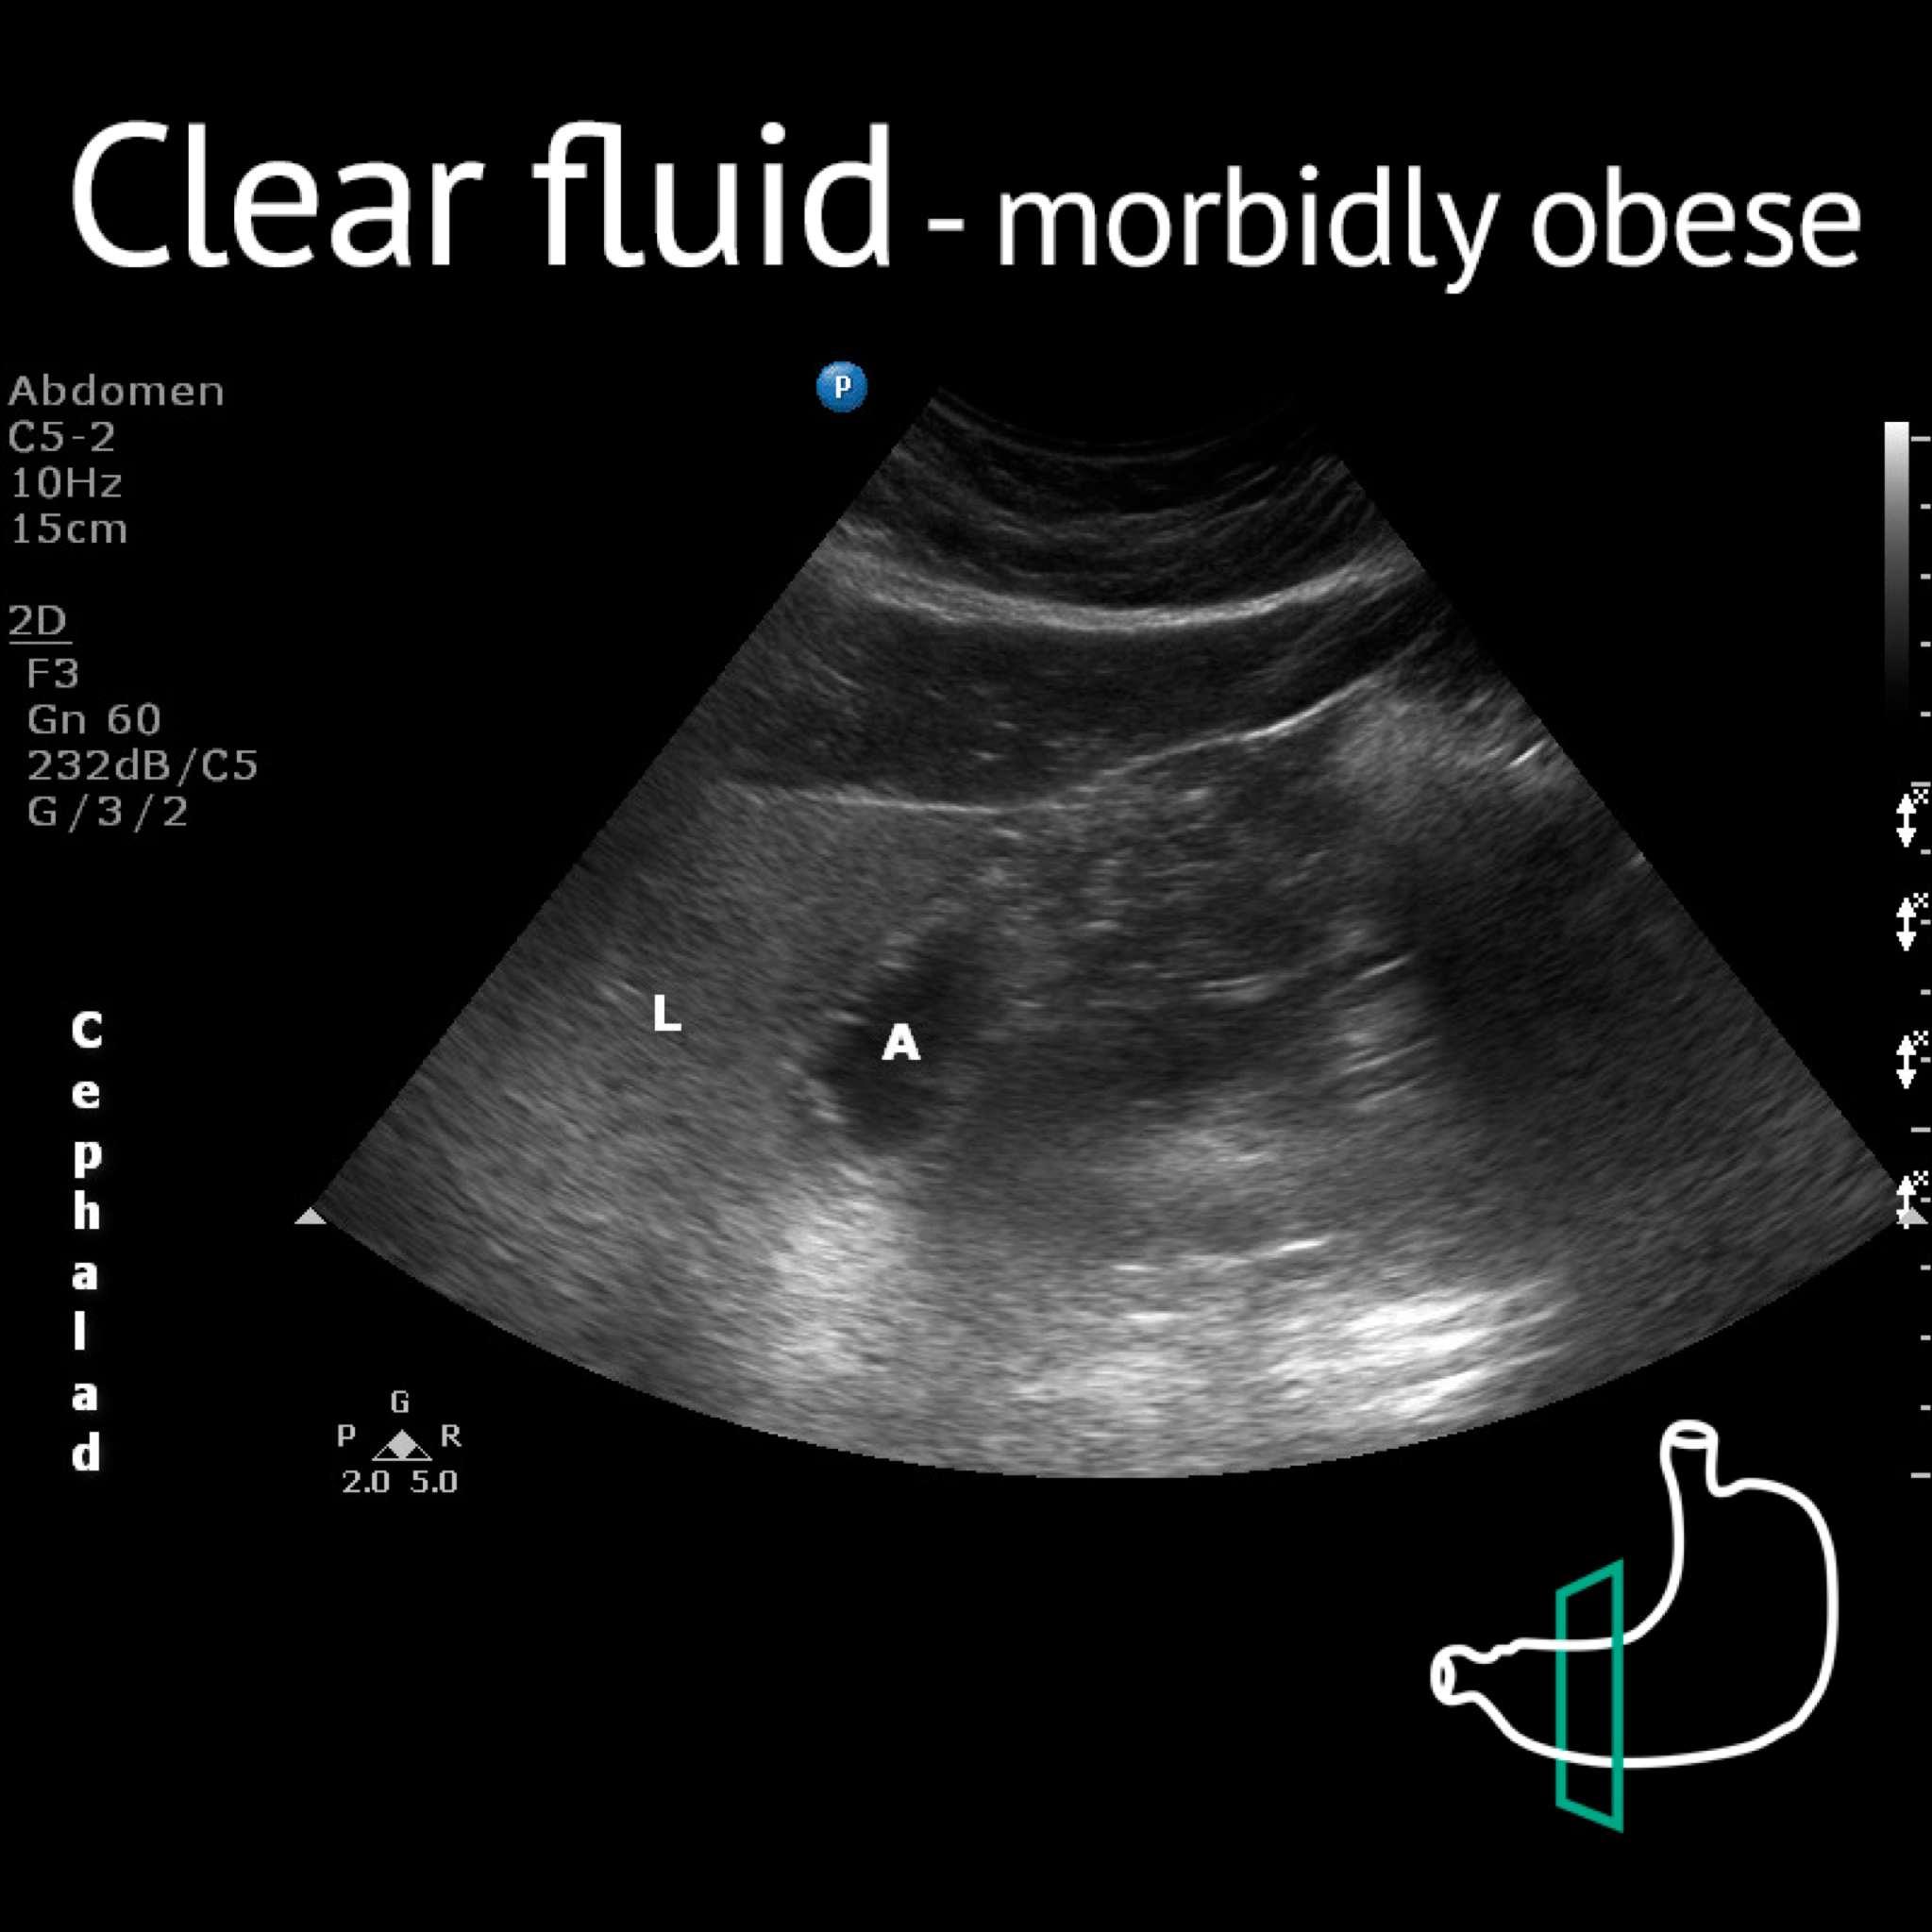

A: antrum; L: liver